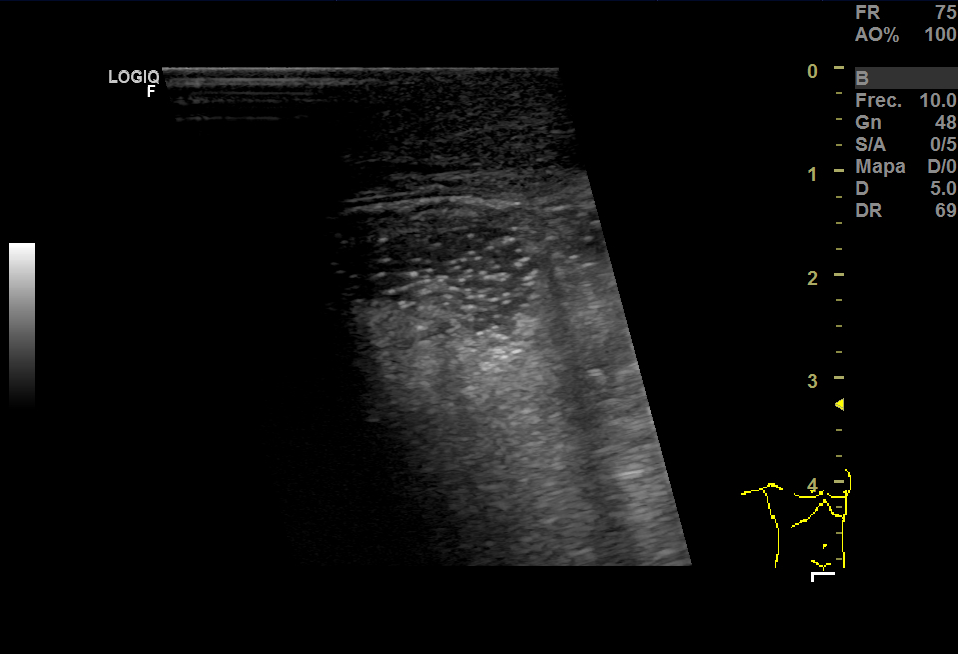

Realizamos una ecografía en Centro de Salud donde vimos que había una herniación derecha y aumento del grosor del tejido celular subcutáneo y, en el espesor, una imagen anecoica que no sabíamos bien a qué podía corresponder.

En la urgencia, realizaron una analítica y encontraron 14.600 leucocitos, PCR 5,13. En Eco testicular, se apreciaron testes de ecoestructura y ecogenicidad normales, epidídimos normales y aumento del grosor del TCSC que impresionaba de celulitis y, en el espesor, una pequeña colección de 15 mm que podía corresponder a absceso o hematoma.